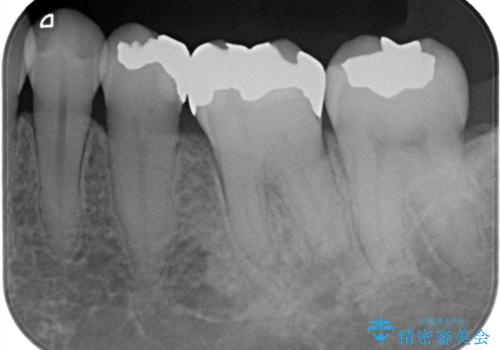

- ご友人との会話中などに、下の歯に入れてあるメタルインレーが見えてしまうのが気になり、やり変えを希望された患者様です。審美性、清掃性に優れたセラミックでの治療を希望されたため、セラミックインレー、クラウンで治療いたしました。